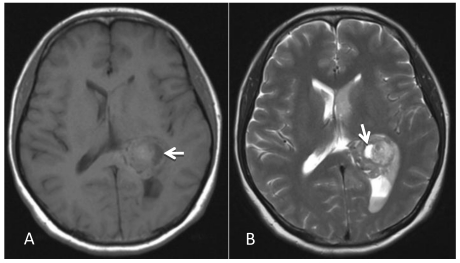

Figure 3.

MRI examination. A-B: A 2.86 cm × 2.68 cm space-occupying lesion was detected in the trigone of the left lateral ventricle; T1WI and T2WI showed mixed signals, and a cystic shadow was noted within the lesion. Slightly high abnormal T1WI and T2WI signals in the bilateral lateral ventricles were observed, and fluid was visible in the occipital horn of the left lateral ventricle (arrow).